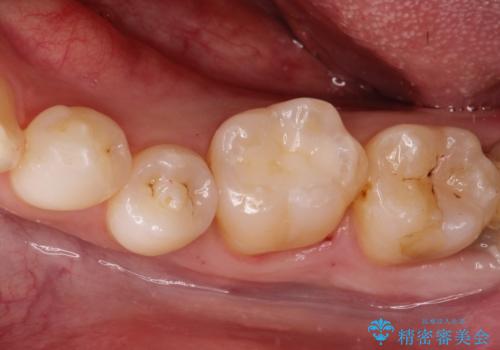

メタルフリー セラミックインレー

- メタルフリーの治療を希望されて来院されました。

セラミックインレーの治療を2回の来院で終了しております

e-max プレスインレーにて修復治療を行っているため適合性及び審美性の高い治療を行うことができます